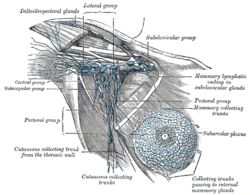

Lymphatics of the axillary region